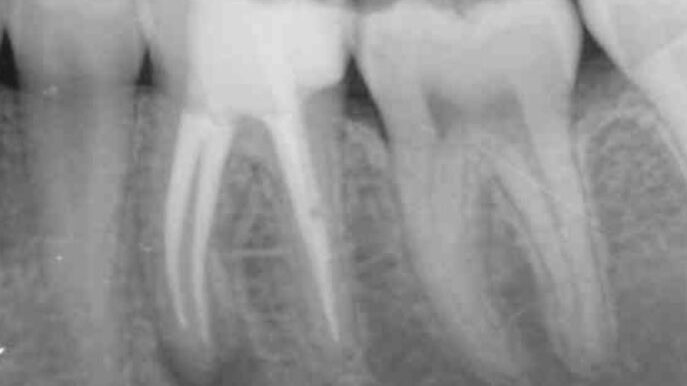

Caso clínico del doctor Marc Llaquet de una reendodoncia del diente 2.4 instrumentado con las limas RetreatAll® para…